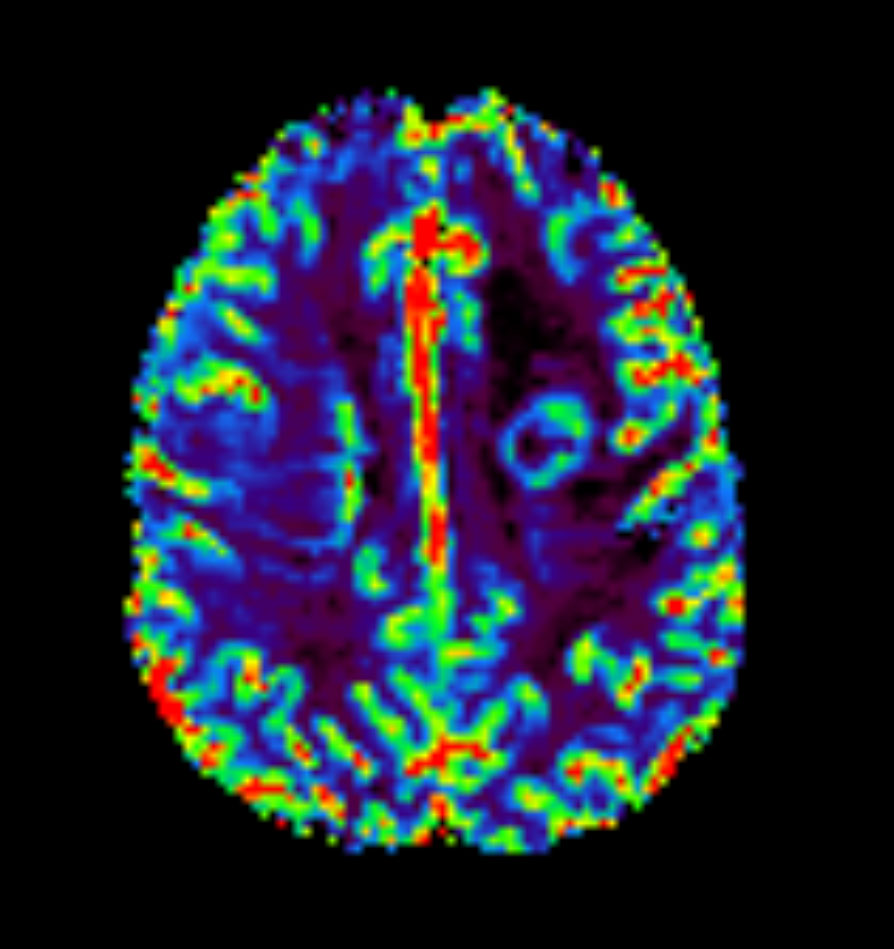

Axial T2* Perfusion - rCBF

Axial T2* Perfusion - TTP